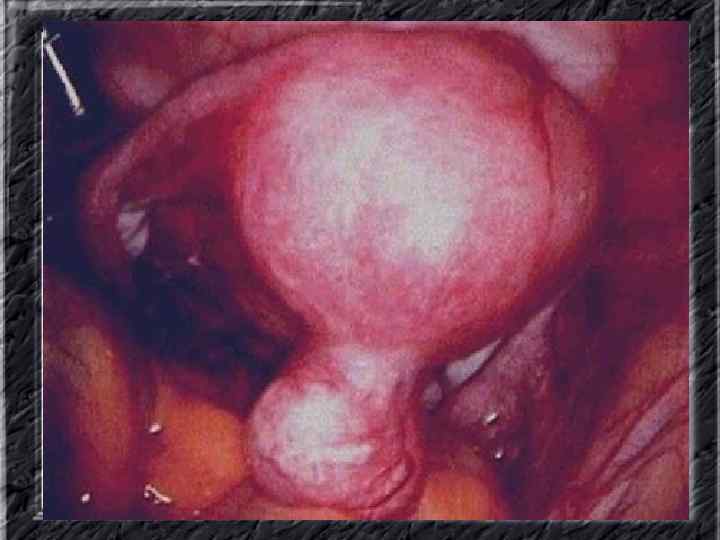

Названия слайдов: • • • Слайд 20. Ультрасонография: диффузная эхонеоднородность миометрия при внутреннем эндометриозе. Слайд 21. Эндометриоз матки: Пять маленьких очажков эндометриоза красно-коричневого цвета по задней поверхности матки; макропрепарат. Слайд 22. Множественная миома матки: видны субсерозные, субмукозные и интрамуральные узлы; макропрепарат. Слайд 23. Большая миома матки, подвергшаяся дегенеративным изменениям ( «красная дегенерация» ); макропрепарат. Слайд 24. Ультрасонография: интрамуральный узел фибромиомы, деформирующий контуры органа. Слайд 25. Ультрасонография: интрамуральный узел фибромиомы, деформирующий полость матки и смещающий эндометрий книзу. Слайд 26. Ультрасонография: субсерозный узел фибромиомы матки с эхопризнаками нарушения питания. Слайд 27. Лапароскопия: субсерозная фибромиома матки. Слайд 28. Лапароскопия: выраженный сосудистый рисунок на поверхности субсерозной фибромиомы матки. Слайд 29. Лапароскопия: выраженный сосудистый рисунок на поверхности субсерозной фибромиомы матки. Слайд 30. Большая цервикальная плоскоклеточная карцинома, которая простирается до влагалища; макропрепарат.

Названия слайдов: • • • Слайд 51. Ультрасонография: интерстициальный и истмический отделы маточной трубы. Слайд 52. Лапароскопия: неизмененная правая маточная труба. Слайд 53. Ультрасонография: многокамерная форма сальпингита. Слайд 54. Лапароскопия: относительно равномерное утолщение маточной трубы при гидросальпинксе. Слайд 55. Лапароскопия: вид маточной трубы при гидросальпинксе. Слайд 56. Гистеросальпингография: неравномерное расширение и деформация маточных труб. Слайд 57. Прервавшаяся трубная беременность: плод; макропрепарат. Слайд 58. Гематосальпингс, развившийся вследствие внутреннего разрыва плодо-вместилища при трубной беременности; макропрепарат. Слайд 59. Лапароскопия: значительное увеличение участка маточной трубы при трубной беременности. Слайд 60. Лапароскопия: скопление крови в полости малого таза в результате трубного аборта.